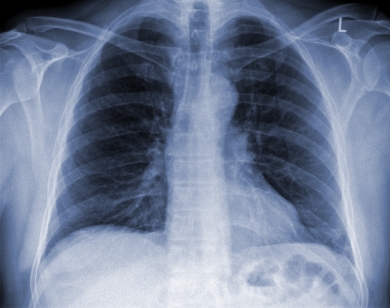

Диагностика микоплазменной пневмонии: Для точного установления диагноза микоплазменного воспаления легких проводят иммунологические и микробиологические исследования. Обязательно проведение рентгенологического исследования легких.

Диагноз атипичной вирусной пневмонии, как правило, ставится путем исключения других возможных причин пневмонии. Для этого назначают рентгенографию и анализ мокроты. Существуют методы, позволяющие выявить сам вирус в организме больного.

Медицинские процедуры, проводимые при заболевании атипичная пневмония: Рентген, Мазок из зева на Хламидии, Мазок из зева на Микоплазму, Мазок из зева на Легионеллез, Серология